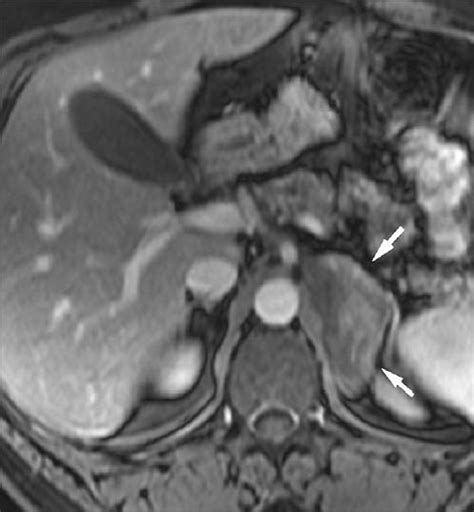

Adenoma in a 46-year-old man. Coronal venous phase ...

Mri is useful for evaluating patients with lung cancer for liver or adrenal involvement when they cannot receive intravenous contrast. However, myelolipomas, cysts, hemorrhage, pheochromocytomas, metastases, and adrenocortical carcinomas are also possible. Finally, a number of nonadrenal pathologic conditions have been reported to mimic adrenal masses at ct. Distinguishing benign from malignant adrenal masses: Incidental masses should be categorized according to diagnostic imaging features, mass size, growth (cf. Adrenal mass characterization using non invasive diagnostic imaging has gained more interest in recent years due to the prevalence of adrenal pathology detected on routine ct examinations performed for clinical conditions that are not related to suspicion of adrenal diseases. The adrenal gland is involved by a range of neoplasms, including primary and metastatic malignant tumors; Foci of fat and punctate calcifi cations;